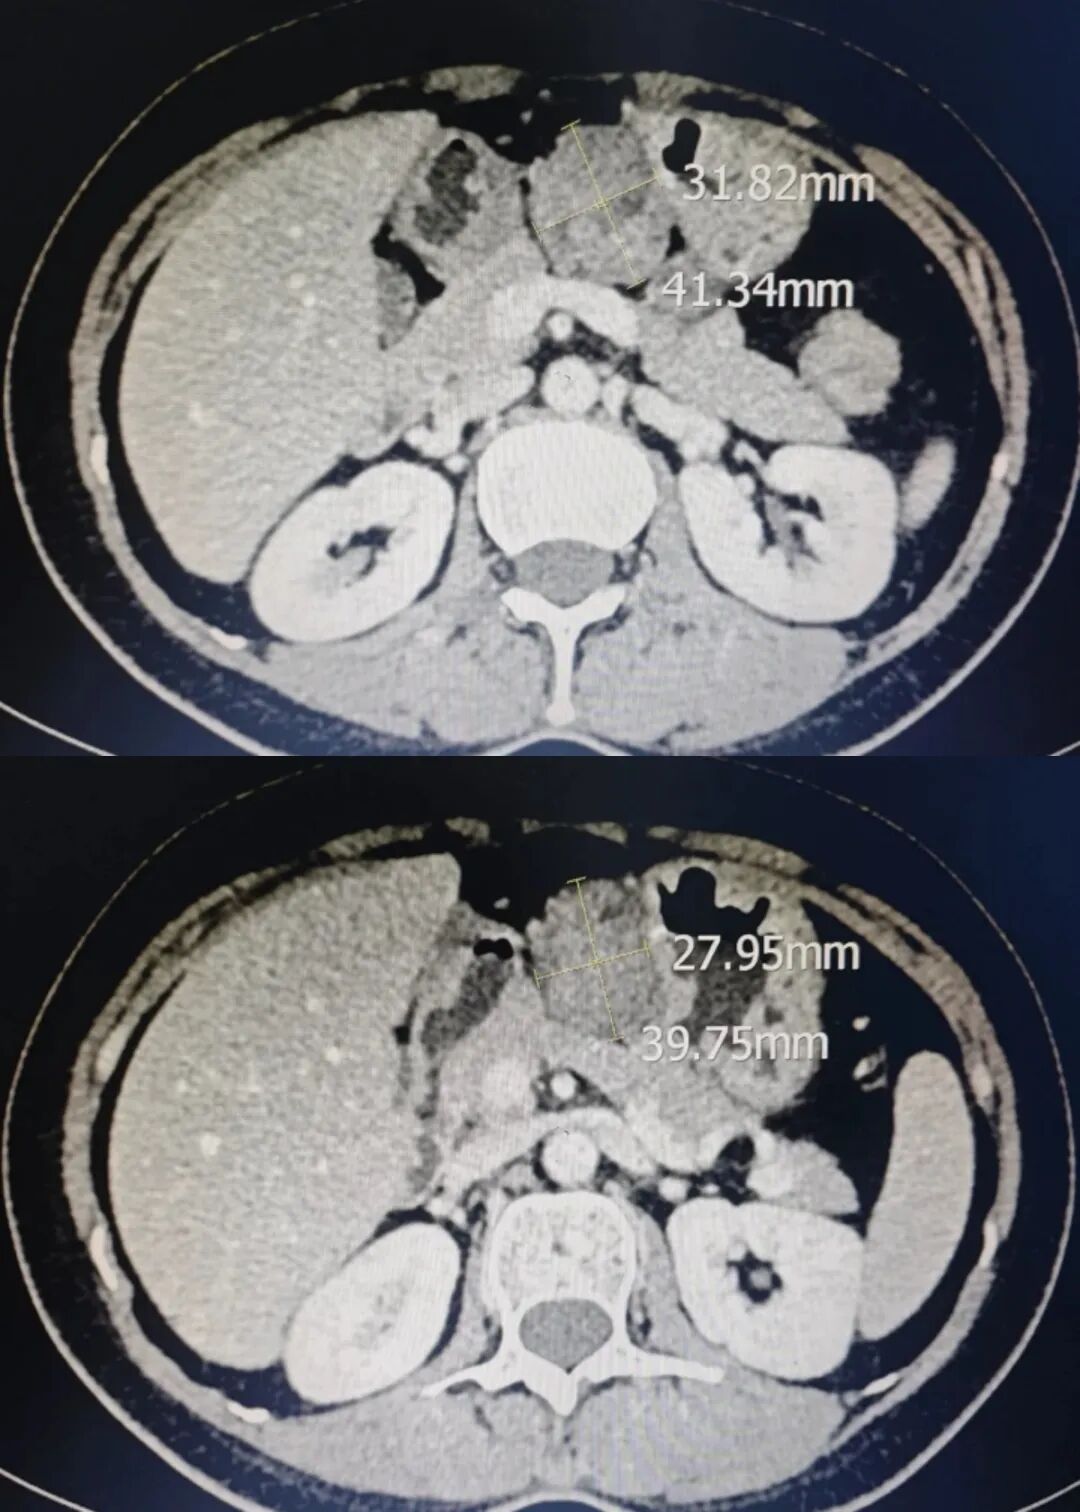

9 月 28 日,云南省曲靖中心医院通过多学科协作(MDT)模式,由微创肝胆外科与妇科团队主导,医学影像中心、麻醉科密切配合,成功实施曲靖地区首例 “NOSES(腹腔镜下全子宫切除术+腹腔镜下卵巢巧克力囊肿剥除术+腹腔镜双侧输卵管切除术+腹腔镜下胃病损切除术+腹腔镜下盆腔粘连松解术,经阴道取出标本)手术”,标志着医院微创外科技术与多学科协作能力迈上新台阶。患者为一名46岁女性,因妇科症状就诊,医学影像中心经精准术前评估,不仅确诊其患有多发性子宫肌瘤、卵巢巧克力囊肿,还同步发现胃窦部占位性病变。若采用传统方案,此类多脏器病变需分两次手术,或单次手术留较大腹部切口取标本,会显著增加患者创伤与痛苦。为此,医院启动 MDT会诊,微创肝胆外科、妇科、医学影像中心、麻醉科专家共同研判后,决定为患者实施 “腹腔镜下全子宫切除术 + 卵巢巧克力囊肿剥除术 + 双侧输卵管切除术 + 胃病损切除术 + 盆腔粘连松解术(经阴道取标本)” 的多脏器 NOSES 联合手术。患者术中生命体征平稳,术后各项指标正常,恢复良好。NOSES 手术(经自然腔道取标本手术)被誉为 “微创中的微创”,核心优势在于根治病变的同时,利用人体自然腔道取标本,避免腹壁辅助切口。本次手术中,团队先在腹腔镜下精准切除胃部病灶及妇科病变组织,再通过阴道完整取出标本,患者腹部仅留数个微小操作切口。与传统腹腔镜手术相比,该术式优势显著。创伤更小:无腹壁辅助切口,术后疼痛轻;恢复更快,患者下床活动早、肠道功能恢复快,可缩短住院时间;美容性佳,腹壁无明显疤痕,更契合女性患者美观需求;心理负担轻,减少患者对手术疤痕的焦虑,提升就医体验。此次多脏器 NOSES 手术的成功实施,不仅是医院在外科治疗领域的一次重要突破 —— 它以 “更小创伤、更快恢复、更优体验” 的实践,践行了医院对微创化、精准化、人性化治疗的长期追求,更生动展现了多学科协作的强大力量。未来,医院将持续以患者需求为导向,加大新技术、新项目研发力度,进一步完善多学科协作机制,切实以技术创新守护群众健康,为区域医疗事业高质量发展注入源源不断的动力。